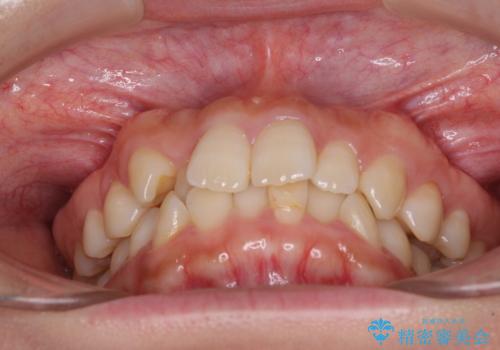

前歯のクロスバイト 目立たないワイヤー装置で速やかに矯正治療

- 前歯のクロスバイトを気にして来院された患者様です。